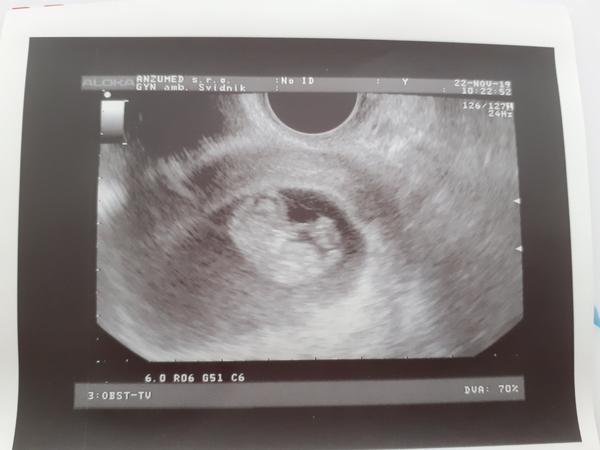

@rachel36a dnes mi to doktorka potvrdila. Som začínajúci 5tt 😍

@rachel36a už máme 24mm a 9+5tt ❤